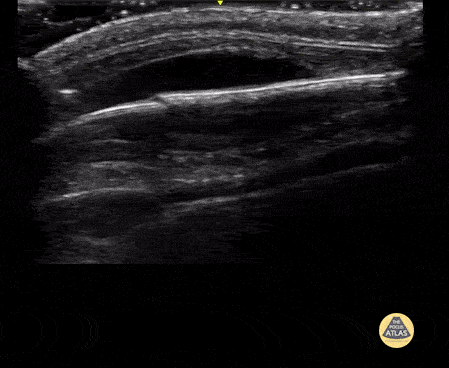

9 month-old presented after a 4 foot fall. There was a small frontal hematoma on exam without step off. POCUS was performed with a high frequency transducer over the area of hematoma, and demonstrates the skull as a hyperechoic linear structure, with nondisplaced discontinuity, indicative of a nondisplaced skull fracture. There is also a hypoechoic collection just anterior to the skull, suggestive of an associated hematoma. Contributor: Allie Grither, MD, St Louis Children's Hospital (Washington University in St. Louis), @AGPemMD